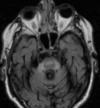

QUAL ACHADO TÍPICO DA RNM DA DOENÇA DE HUNTINGTON?

ATROFIA DO CAUDADO E PUTÂMEN

PACIENTE COM ESSA RNM + DM PENSAR EM QUAL DISTURBIO DO MOVIMENTO?

COREIA METABÓLICA - HIPERGLICEMIA NÃO CETÓTICA TC: HIPERDENSIDADE ESTRIATAL RNM: HIPERSINAL NO T1 c/ t2 e flair variáveis (geralmente hipo)